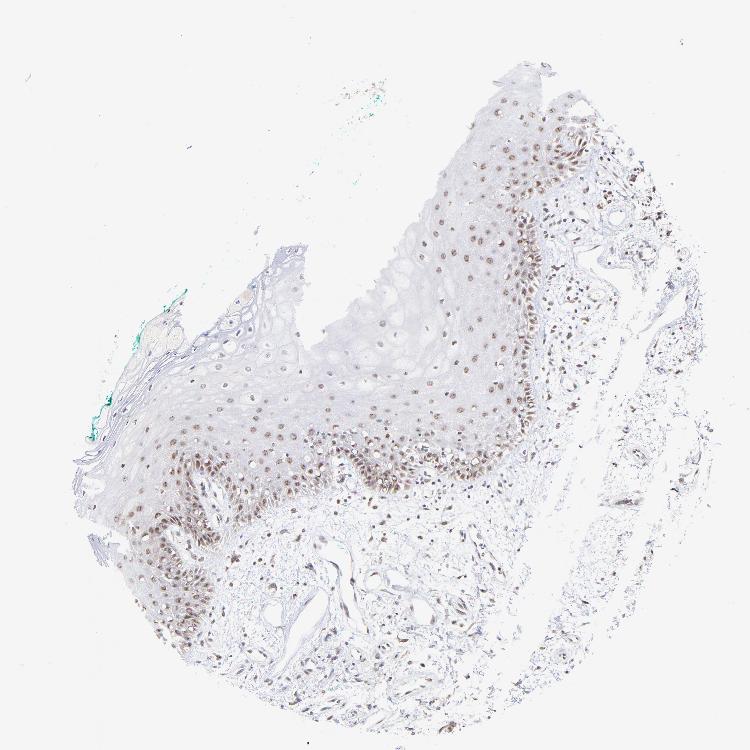

TISSUE PRIMARY DATA ORAL MUCOSA Show tissue menu

ORAL MUCOSA - Antibody stainingi

Antibody staining in the annotated cell types in the current human tissue is reported as not detected, low, medium, or high, based on conventional immunohistochemistry profiling in selected tissues. This score is based on the combination of the staining intensity and fraction of stained cells.

Each image is clickable and will lead to virtual microscopy that enables deeper exploration of all samples and also displays staining intensity scores, fraction scores and subcellular localization as well as patient and tissue information for each sample.

Antibody HPA003142

Squamous epithelial cells Not detected